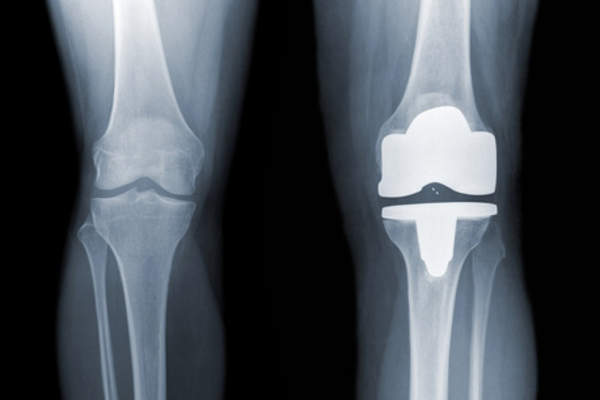

有哪些风险和潜在的并发症?

什么是你的程序的成功率是多少?

病人应该知道成功率去一个特定的手术和外科医生。

什么是这个过程的并发症发生率?

请问你的速度与其他外科医生比较?我需要看看其他地方?